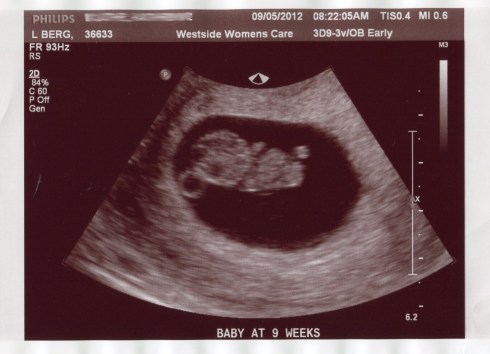

Our first ultrasound went well. They tried to do it on my belly first but our biscuit was too small to see so they ended up doing a vaginal ultrasound. It was a little unpleasant but so worth it to see our little bean squirming around in there! The baby’s Crown to Rump measurement put me at 9 weeks 3 days – about 4 days farther along than I had thought, making my new estimated due date April 7. We also saw the heartbeat and it was somewhere around 180 beats per minute. As we watched our baby do a happy dance, I cried from a mix of joy and relief. Our baby was healthy. It had a heartbeat. Everything was perfect. What a blessing from God!